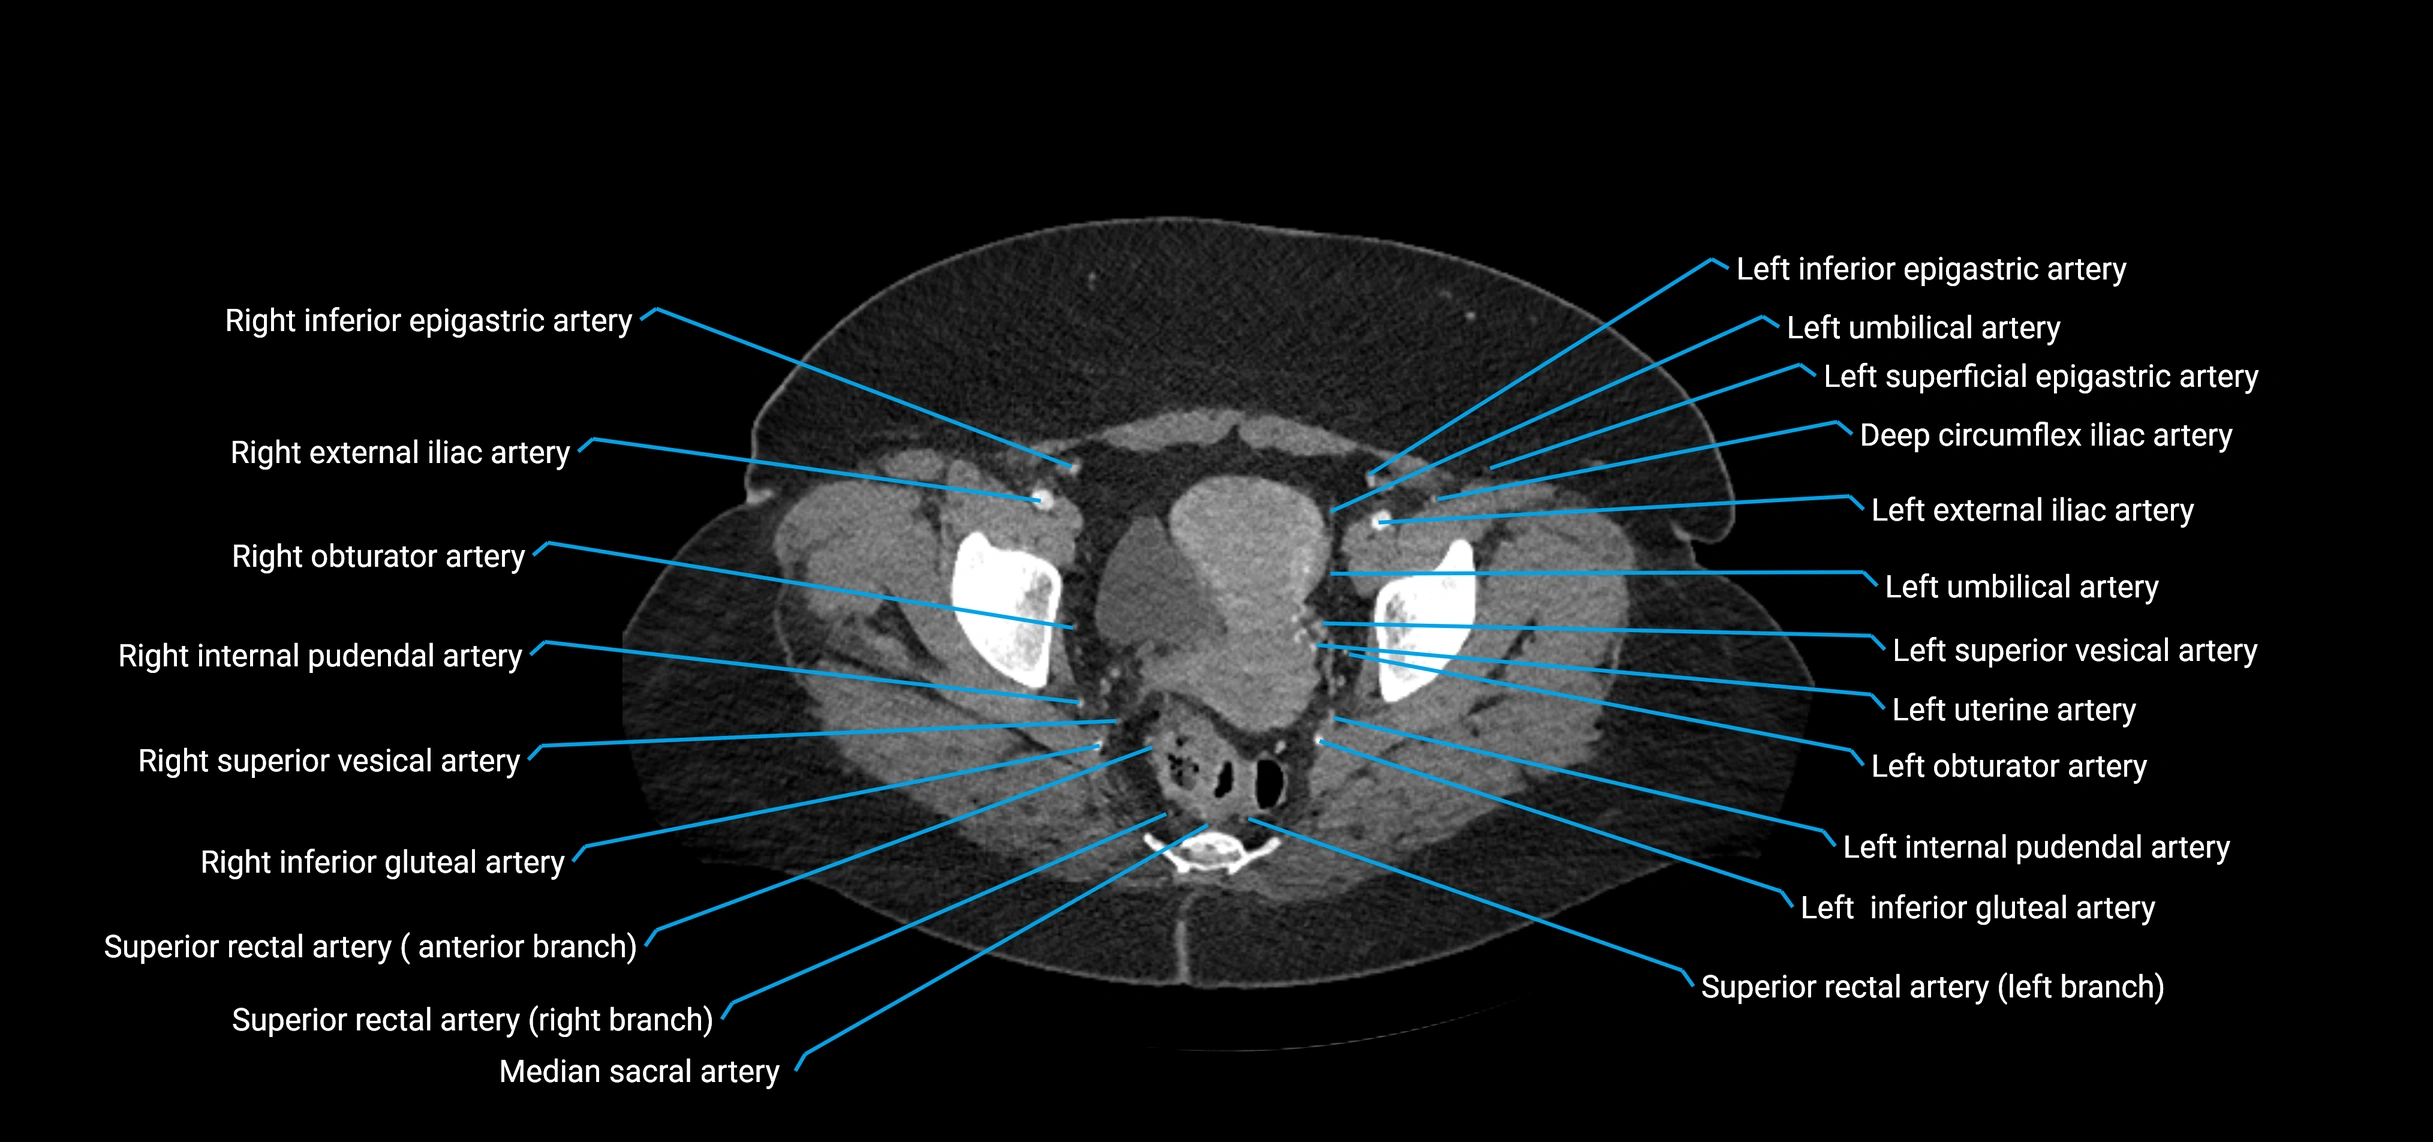

Contrast-enhanced CT (CTA):

• Gold standard for abdominal aortic imaging

• Provides excellent detail of lumen, wall, aneurysm, thrombus, and branch vessels

• Multiplanar and 3D reconstructions help in aneurysm measurement, stent graft planning, and dissection evaluation